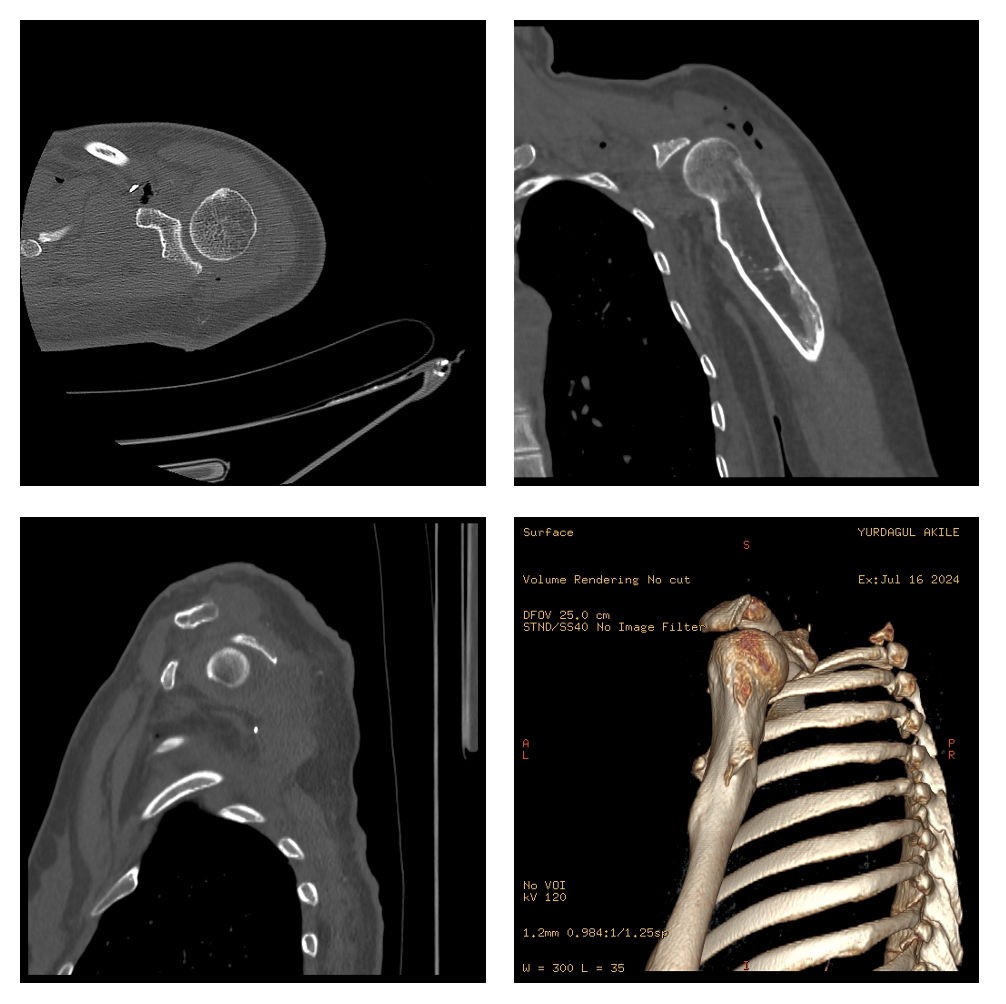

Ameliyat Öncesi: Tomografide skapulada destrüksiyon görünmekte.

Ameliyat Sonrası: Tomografide rezeksiyon sınırı ve kalan glenoid eklem yüzü görünmekte.